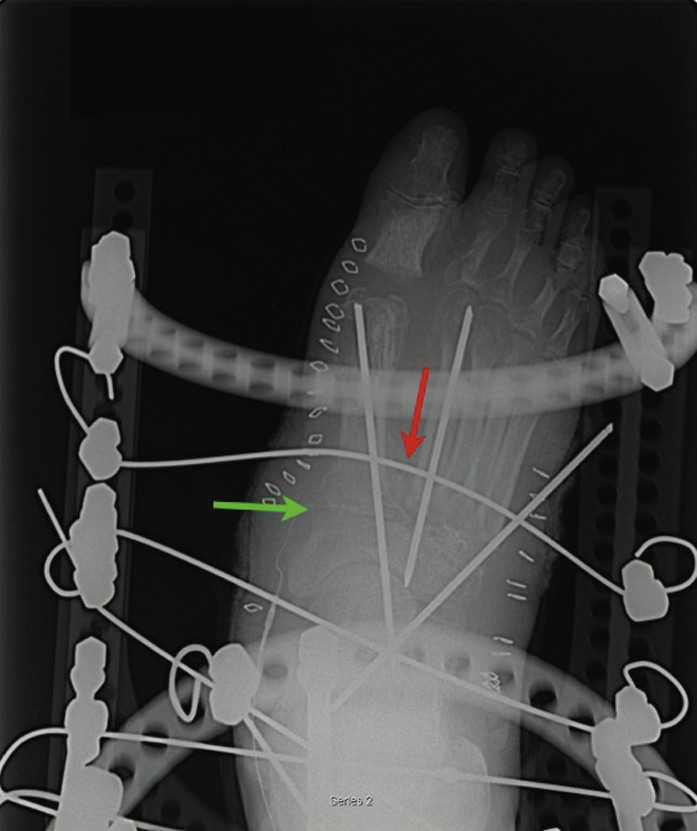

Surgical interventions vary from Achilles tendon lengthening and exostecomy to foot reconstruction. Achilles tendinopathy leading to equinus is a contributor to midfoot dislocation and ulceration. The Achilles tendon is less elastic in Charcot foot.25 In many cases, surgeons perform tendo-Achilles lengthening in combination with medical therapies or more advanced surgical procedures. Exostectomy is a viable option for medial plantar prominences (i.e., navicular). However, this procedure has a higher rate of failure when surgeons attempt to employ it for central and lateral prominences.26 When a surgeon decides to reconstruct, he or she should isolate and fuse the affected joint. The choice of internal or external fixation depends on the quality of the bone. Generally in the Charcot syndrome, the bone stock is poor and external fixation results in better compression with fewer fixation failures. When one uses internal fixation, locking plates may prevent backing out of hardware. The operative technique depends on the pathology but typically involves resection of the affected joint surface. When it comes to midfoot deformities, utilizing a plantar-based wedge resection across the tarsometatarsal joint or naviculocuneiform joints is an option. Apply the external fixator with two tibial rings for stability and drive the wires proximal and distal to the fusion site. One would walk the distal wires back on the foot plate. This provides transverse plane compression across the fusion site. While postoperative recommendations vary, we have found that post-op non-weightbearing reduces complication in Charcot midfoot fusions that have been fixated externally.27 For rearfoot and ankle arthrodesis in the Charcot foot, the technique is slightly different. One would use two tibial rings but the decision to use a talar ring depends on surgeon preference. The addition of this ring allows one to isolate the subtalar joint or the ankle joint for compression. Other methods can accomplish similar compression without completely isolating the non-operative joint. Alternatively, if there is severe frontal plane deformity of the ankle or subtalar joints and both joints require fusion, one may consider intramedullary rod fixation.28 In rearfoot and ankle deformities, dynamization with protected weightbearing after surgery might improve union rates. However, this has not specifically been studied with regard to the Charcot foot. External fixation is associated with a high rate of complications (pin tract infections and wire breakage). However, if physicians recognize these complications early, they can easily address these issues and they are non-limb-threatening.29